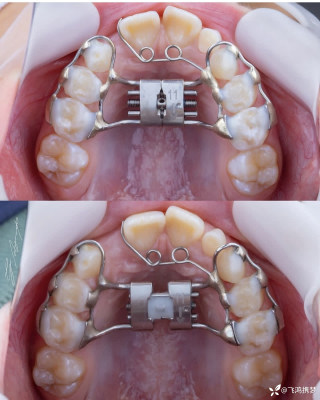

烧伤整形邹普功烧伤科医师

活动背景和目的:我从去年九月份陆续在丁香园写了几十帖有关腋臭微创手术的帖子,受到很多同行老师的关注及跟帖,其中有很多同行老师也在尝试用我的这种方法治疗狐臭,并且收到很好的效果。随着站内外科同行对狐臭微创手术的关注度日渐增高,近期受丁香园邀请,特举办一次关于狐臭微创手术的跟学练活动。这也是本人根据临床工作中的一些手术案例总结的经验,分享给大家一起交流学习。让我们一起做好除臭这件事!各位站友可点击下面狐臭专场链接交流学习(包含本人视频操作教学详解、常见问题讨论和各位站友同行的手术佳作):https://3g.dxy.cn/newh5/view/nodeActivityTopic/270第一期我给大